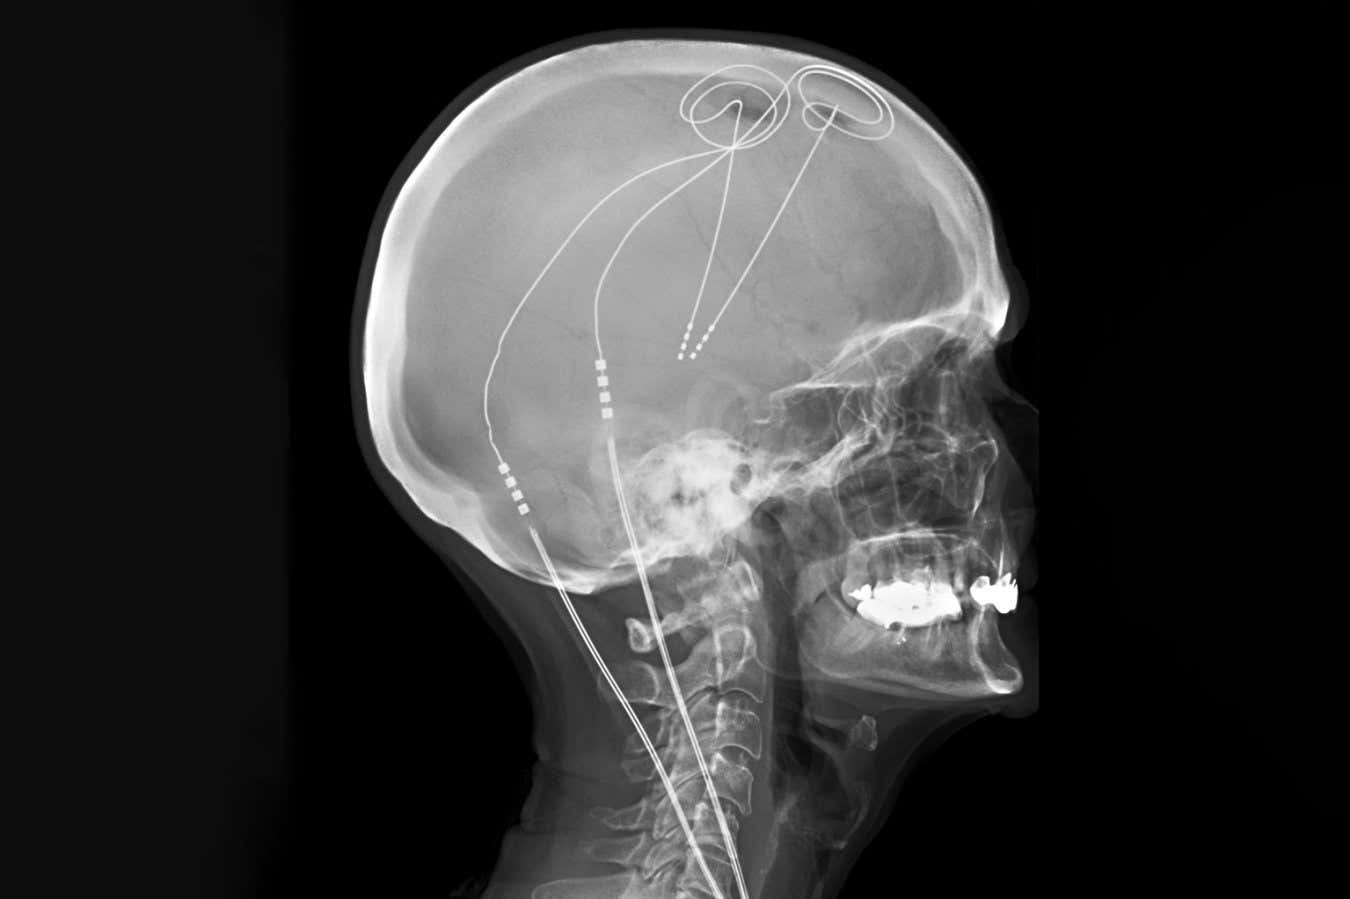

Deep brain stimulation is already used to treat Parkinson’s disease

Living Art Enterprises/SCIENCE PHOTO LIBRARY

Deep brain stimulation (DBS), which involves stimulating the brain using tiny electrodes, has shown promise but has inconsistent results. Traditionally, the same brain areas are targeted in a one-size-fits-all approach, despite evidence suggesting that pain arises from different circuits in different people.

The researchers next used machine learning to identify and distinguish between the electrical activity that occurred when the individuals experienced high or low levels of pain. They then implanted permanent DBS electrodes into each participant, which were personalised to monitor their brain activity and deliver optimal stimulation whenever pain-related activity was detected, and to deactivate when they were asleep.